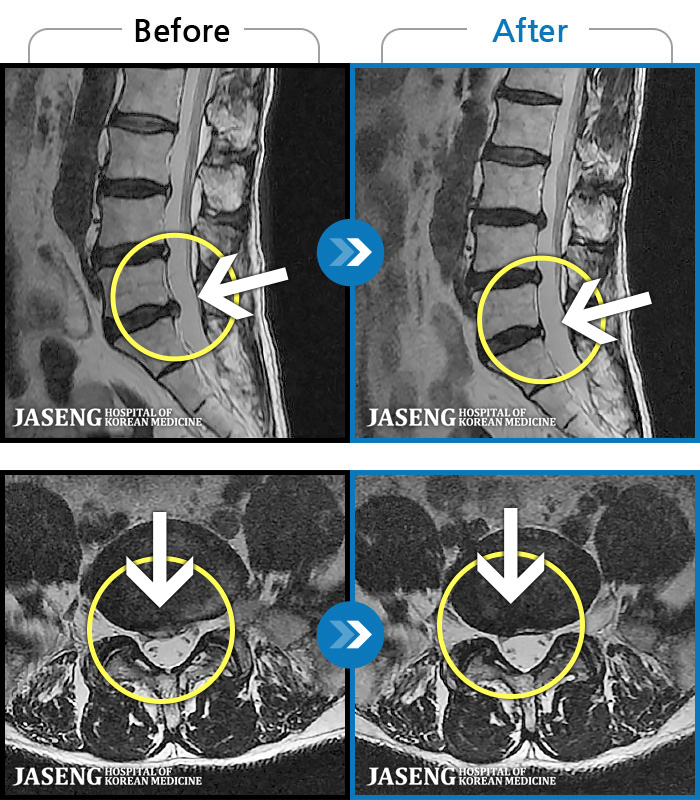

1,240 MRI ũ ʸ Ȯϼ.

[ؿ] 24.10.10~25.04.23